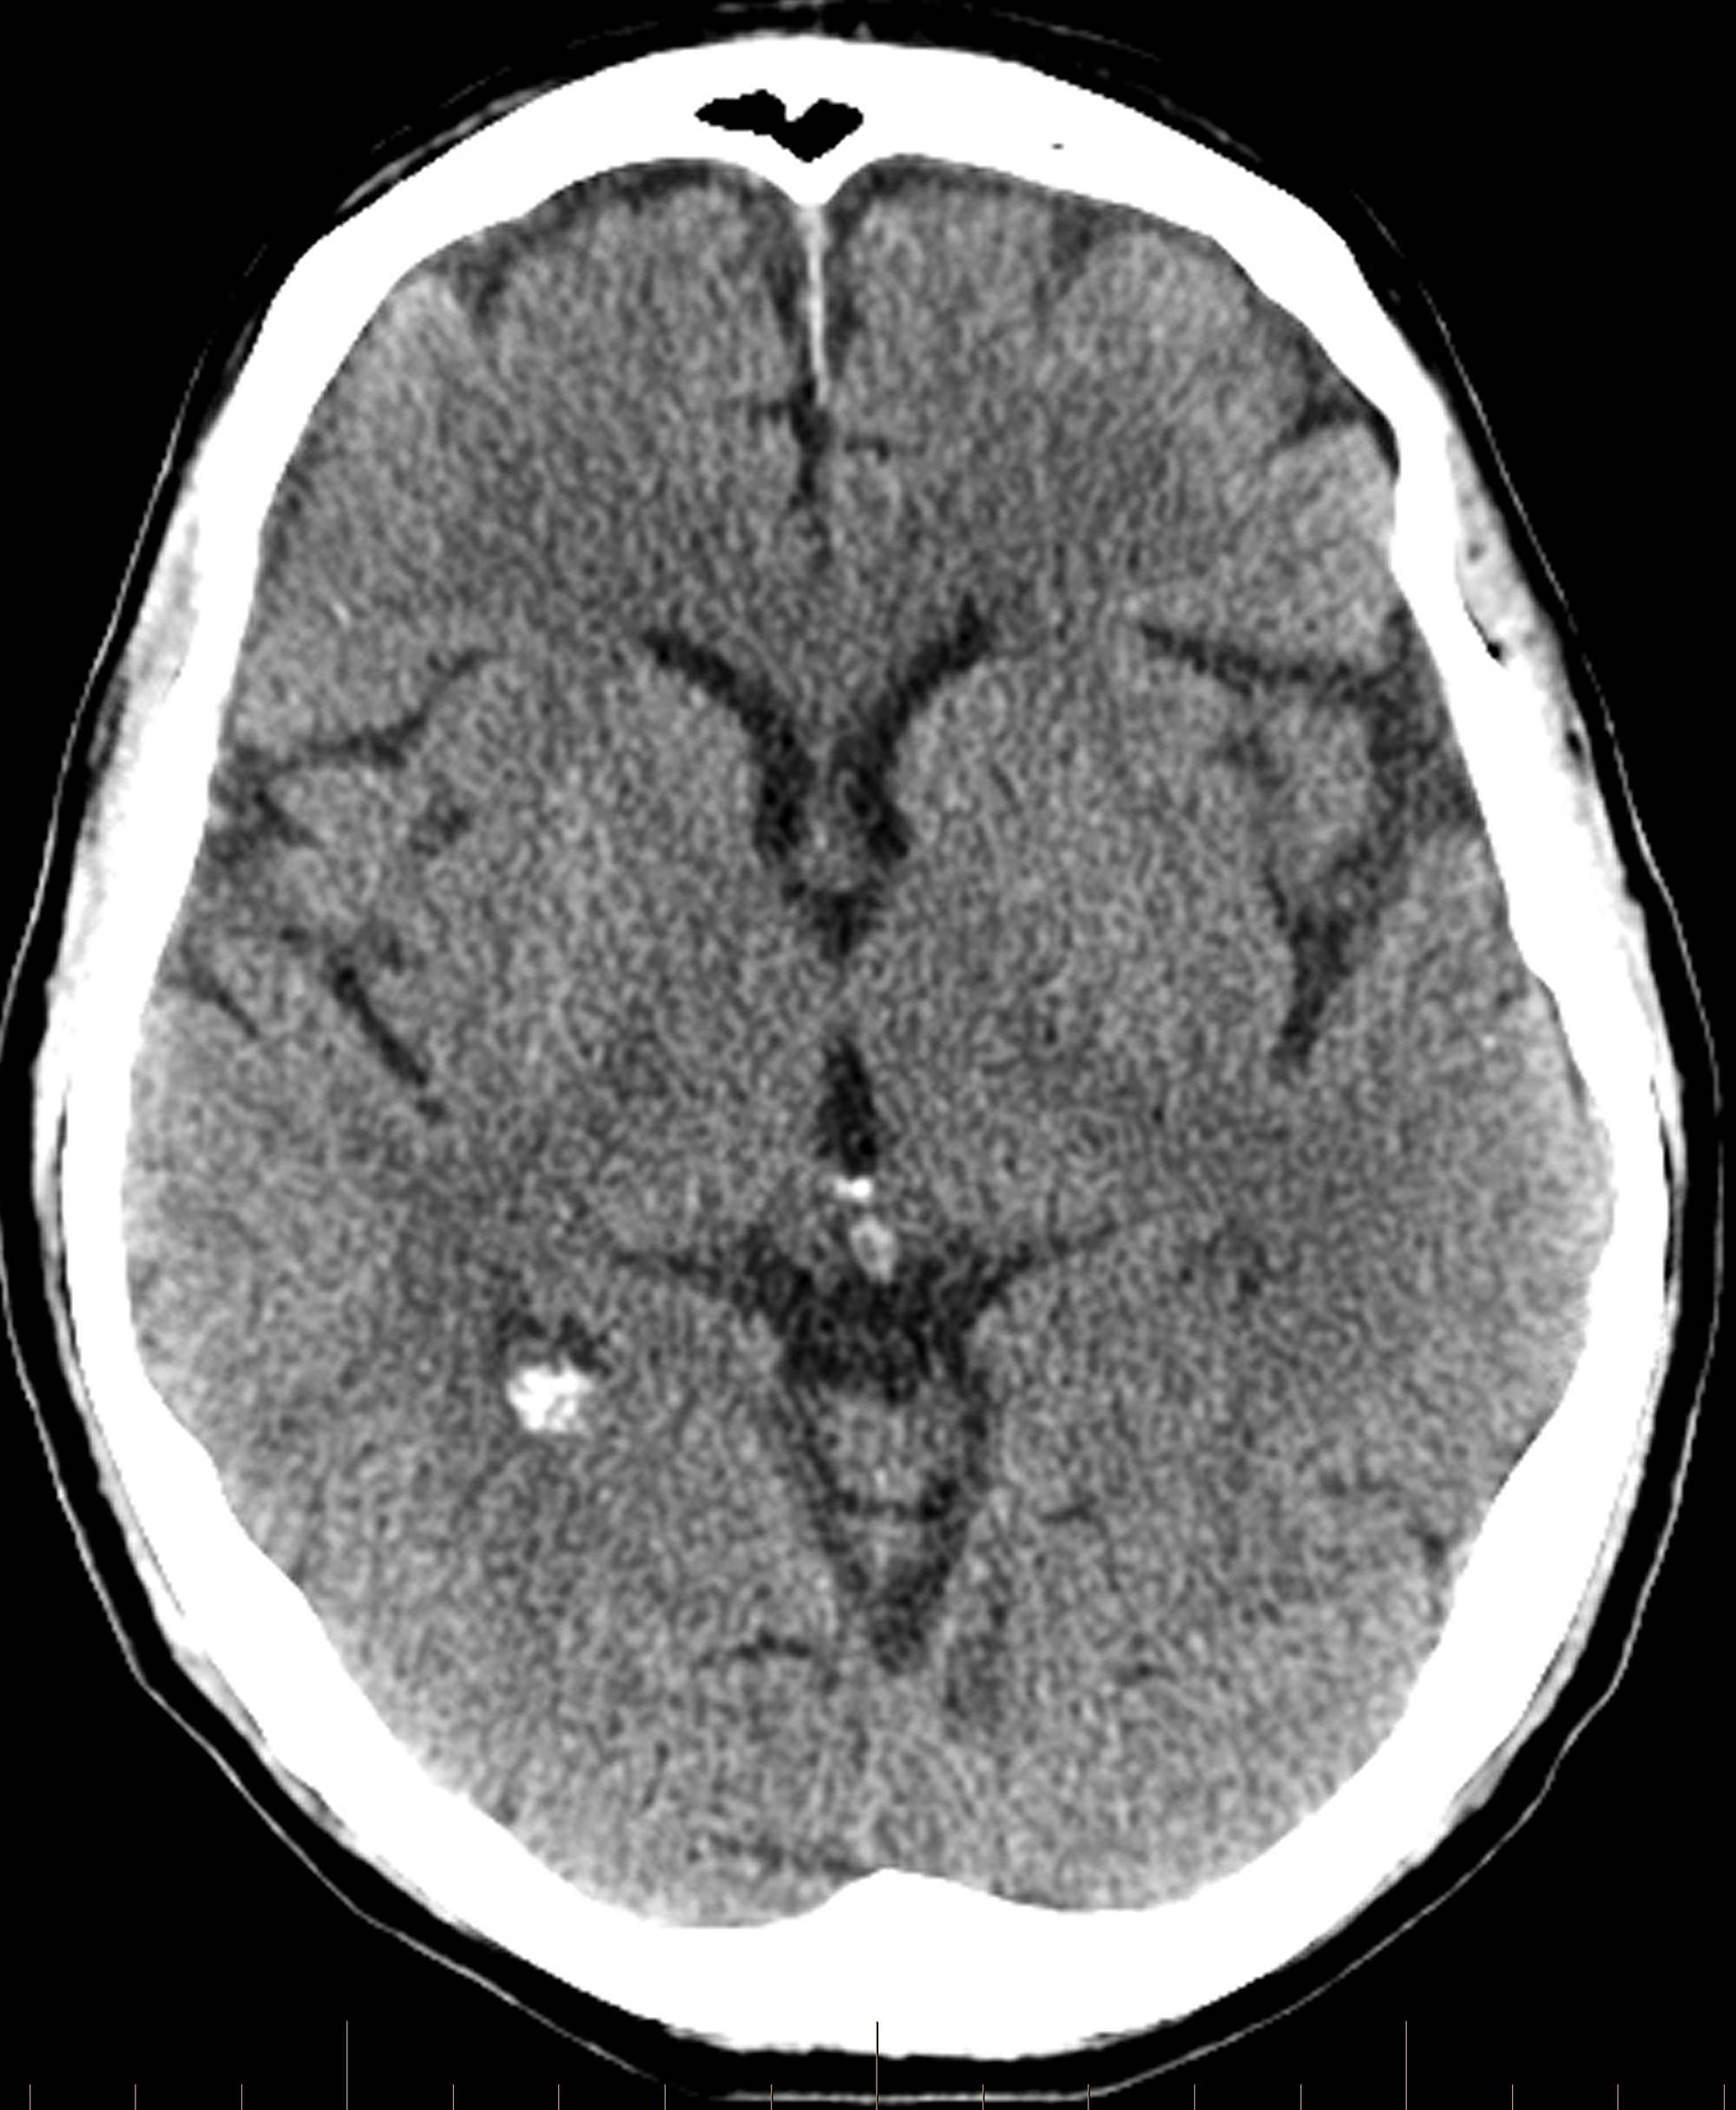

Follow-up head computed tomography (CT) revealed no hemorrhage or acute infarct (Figure 4).